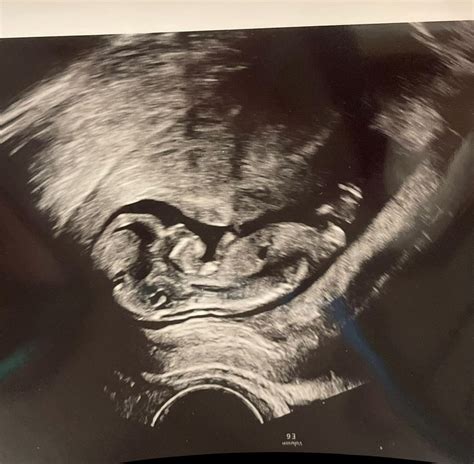

Ultrasound scan of a fetus

The 11 week ultrasound is typically performed either abdominally or transvaginally, depending on factors such as your body type and the position of the uterus. For most women at 11 weeks, an abdominal ultrasound is sufficient, where a transducer is moved over the belly with gel. However, if a clearer image is needed, a transvaginal approach may be used. The entire process is generally painless, though it can feel a bit cold due to the conductive gel.

During the appointment, the sonographer or doctor will focus on several key aspects to ensure the pregnancy is progressing as expected. They are not just looking for a heartbeat; they are assessing anatomical development and ensuring the pregnancy is located safely within the uterus. It is a moment of wonder for many, as you can often see the baby moving, though you may not feel those movements yet.

By the 11th week, your baby is roughly the size of a lime or a Brussels sprout, measuring about 1.5 to 2 inches long. Despite their small size, they are incredibly active. During the 11 week ultrasound, you might be surprised to see your baby performing various movements, such as curling their toes, stretching, or even hiccuping.

• Movement: You will likely see the baby wriggling and stretching, which is a sign of healthy neuromuscular development.